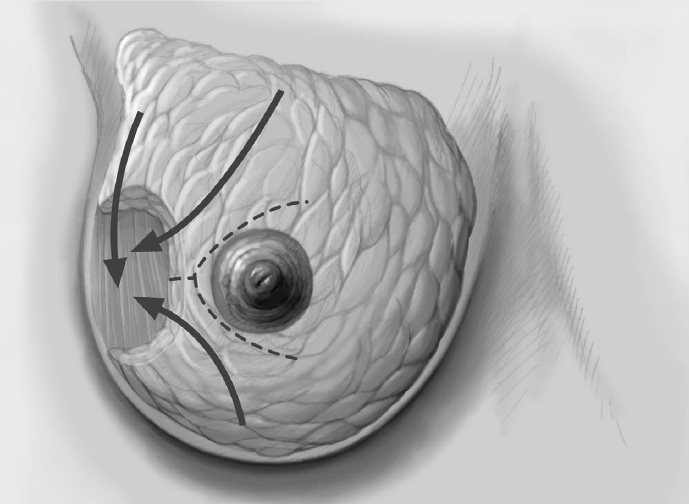

The adjacent parenchyma is mobilized subcutaneously so that the defect can be filled with lobes of breast tissue. Mobilization means exposing the breast relative to the skin or muscle to achieve adequate mobility of < 25% or > 25% as required.

Tension-free approximation for complete intramammary cover of the defect

To cover the defect, the glandular lobes are mobilized from the adjacent parenchyma after subcutaneous dissection. The principle of intramammary lobe creation is to mobilize large parts of the breast (> 25%) either relative to the skin or relative to the pectoralis muscle. This “liberation” of the breast from one of its two planes of fixation allows adequate dissection and rotation of sufficient breast tissue. The Y-flap and rotation flap shown in Chapter 3.2.1 are examples of intramammary dissection.

The mobilized breast lobes are rotated into the defect and approximated by interrupted sutures. Complete covering of the defect is desirable.